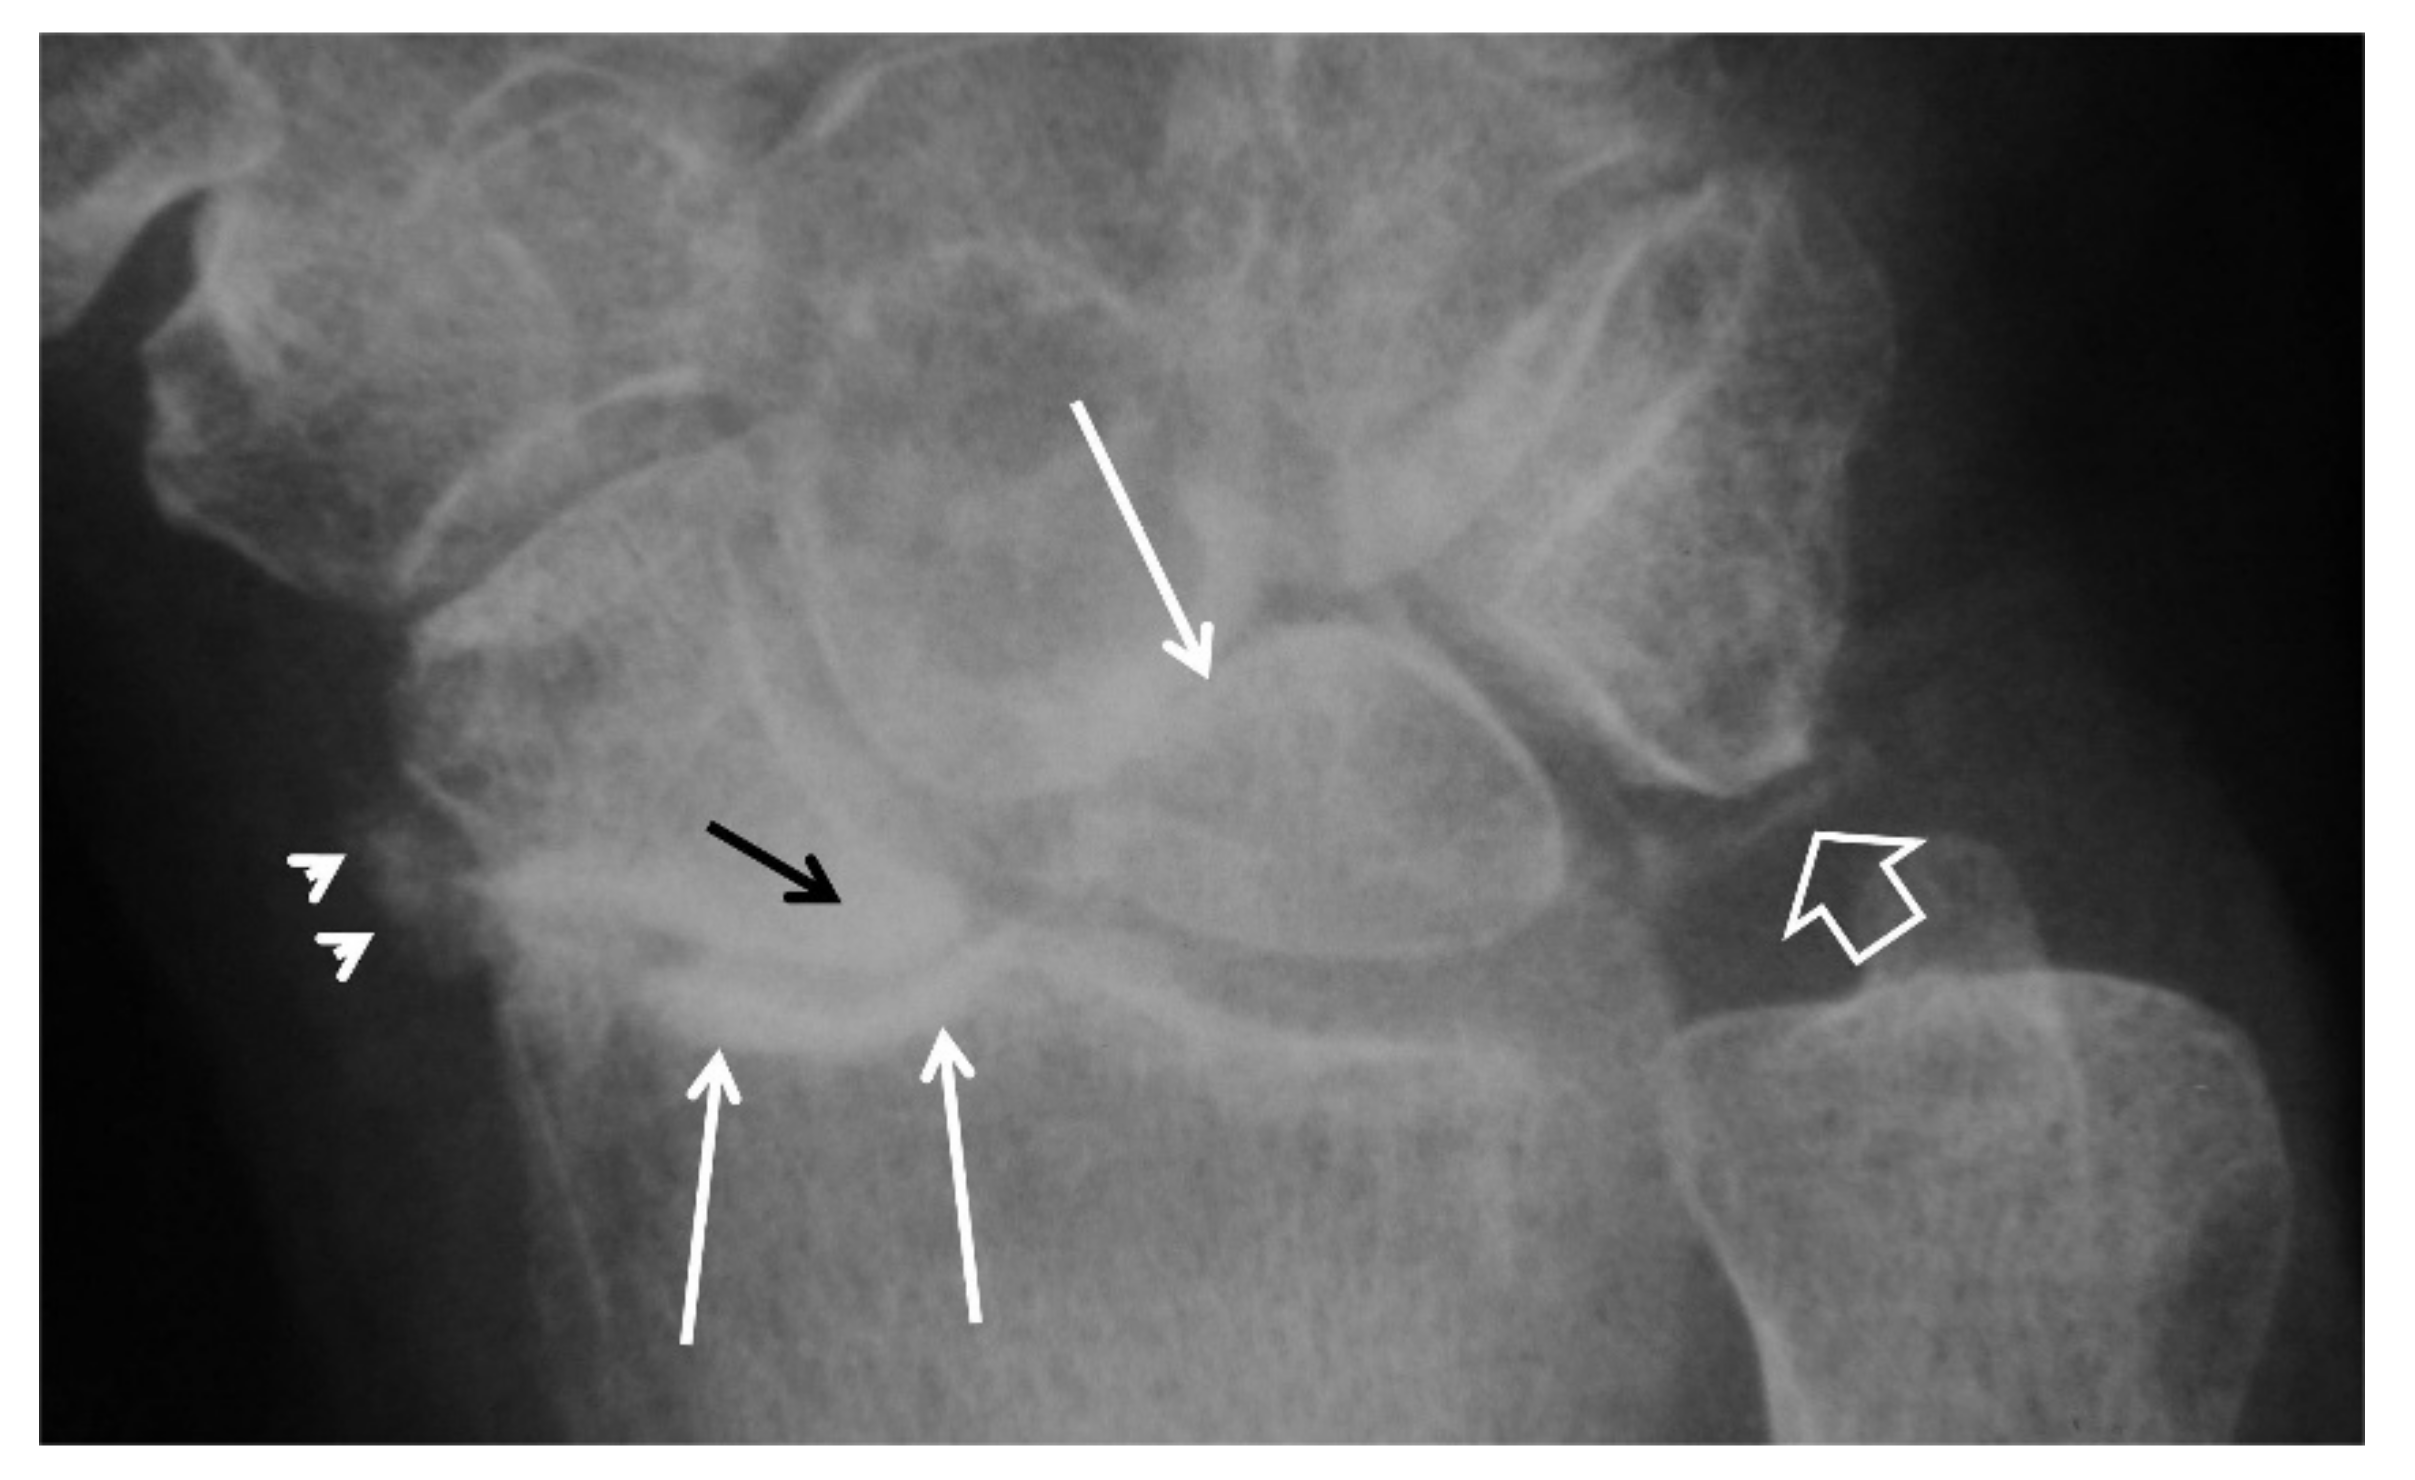

Figure 13.

A 41-year-old male patient with a scaphoid fracture 5 years prior to current imaging and persistent pain and functional impairment during the last 2 years. (A) PA radiograph showing proximal pole osteosclerosis in keeping with osteonecrosis (open arrow) and radial radioscaphoid joint space narrowing with minimal subchondral sclerosis in keeping with SNAC stage I disease (arrow). (B) Coronal T1w MR arthrographic image showing irregularity of the radioscaphoid space (arrowheads) and low signal intensity of the scaphoid bone marrow suggesting global osteonecrosis (arrows). Subchondral sclerosis suggesting early osteoarthritis is shown on both images in the proximal capitate (small arrows).